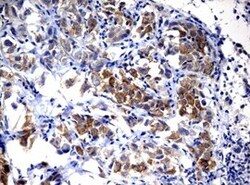

- Immunohistochemical staining of paraffin-embedded human large B cell lymphoma with ALK translocation using anti-ALK mouse monoclonal antibody. (TA801287, 1:50; heat-induced epitope retrieval by 1mM EDTA in 10mM Tris, pH8.0, 120°C for 3min)